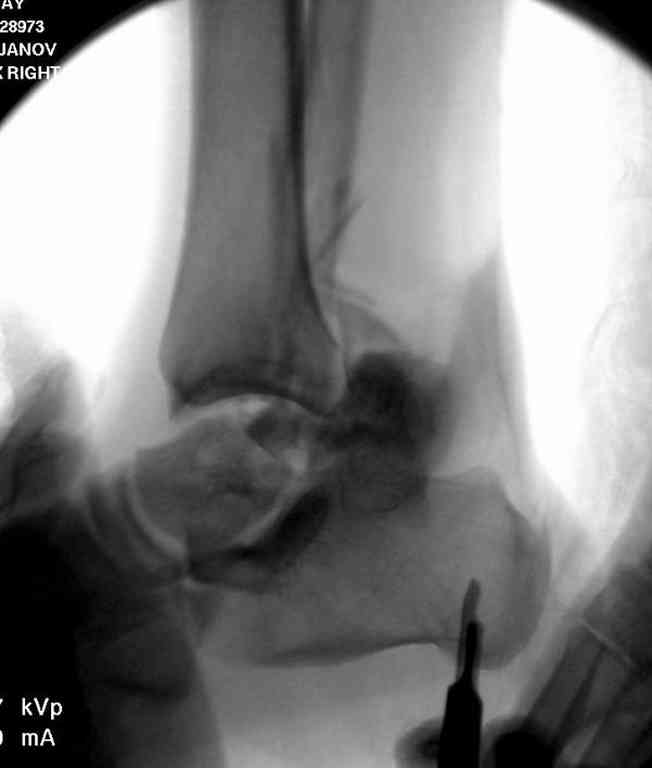

Вчера провели фиксацию.

Из-за многооскольчатости дистальной части малоберцовой, где невозможно было провести фиксацию шурупами, перелом зафиксирован подпирающей пластиной, которая должна служить дополнением отсутствующей дистальной части малоберцовой (lateral cortex substitute).

Для стабильности два шурупа на синдесмоз.